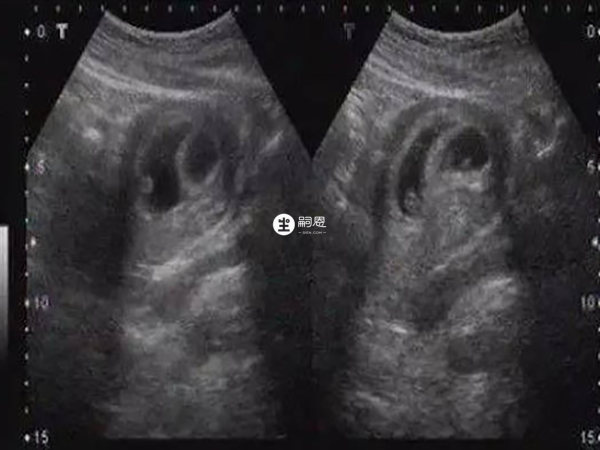

大家可以看到圖中女寶的生殖器結構,上面有類似於線條的一槓,這就是女寶胎兒的外生殖器結構,有的時候b超看到是一條線,大多時候是三條,孕周大了之後,這個時候性別特徵不僅很明顯,而且非常清晰好分辨。